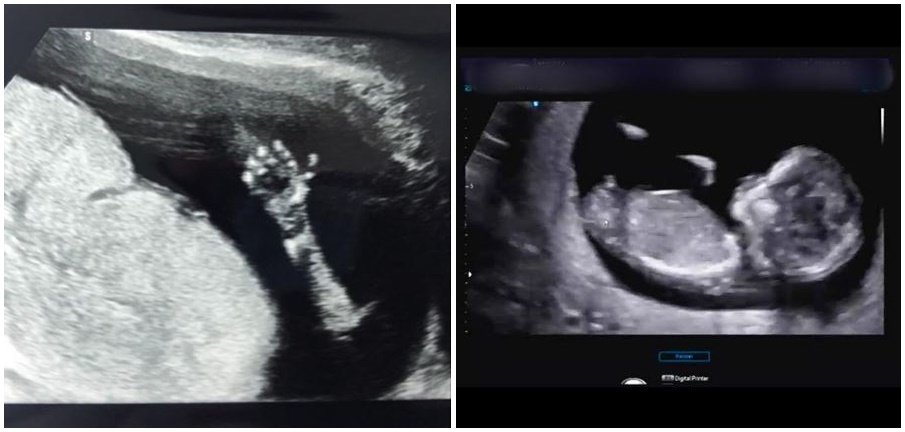

22일 구재이는 자신의 인스타그램에 태아 사진을 올리며 임신 소식을 알렸다. 구재이가 공개한 사진에는 태아의 발과 손, 머리 형태 등이 분명하게 보였다.

구재이는 "갑자기 찾아와 깜짝 놀라게 한 리보. 아직은 모든 것이 낯설고 새롭고 놀라움의 연속이지만 건강하게 16주를 지나며 잘 자라고 있어 감사한 마음뿐이네요"라는 글을 남겼다. 이어 "반갑다 리보야"라며 아이에 대한 애정을 드러냈다.